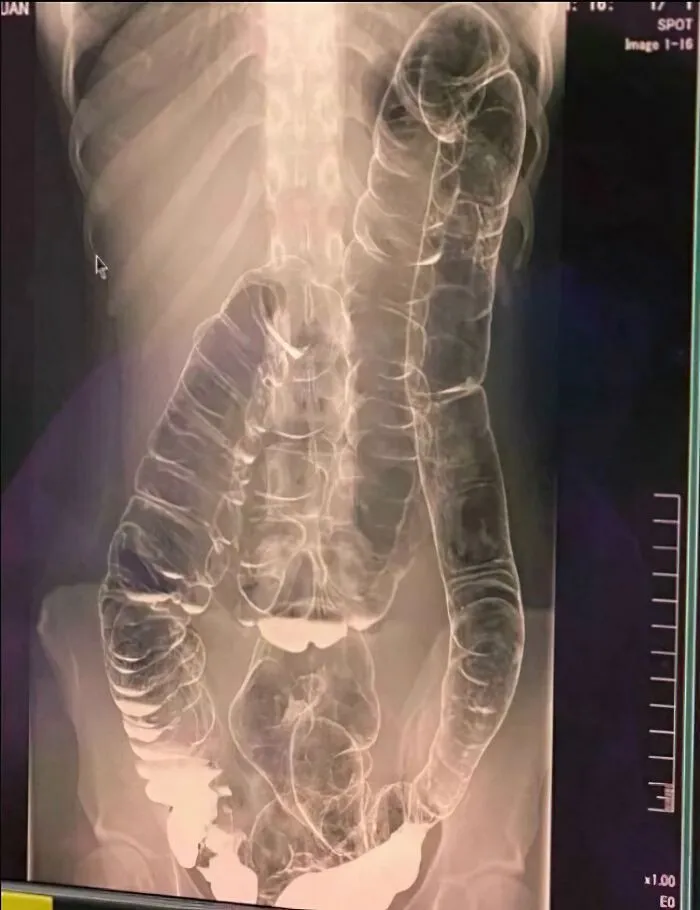

12. Так выглядит запор через 19 дней. Вот дерьмо!

Это изображение бариевой клизмы с двойным контрастированием.